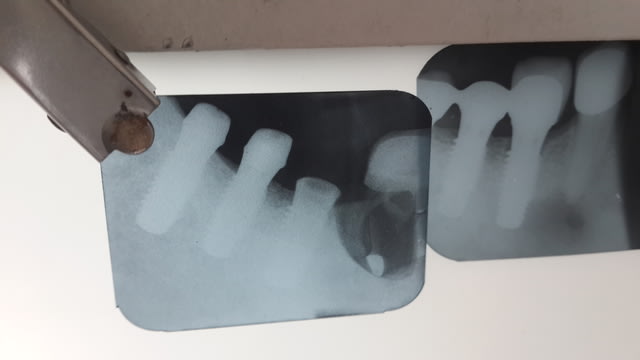

tu peux faire une autre radio un peu mieux centrée sur l'implant?

çà ressemble beaucoup à un naturactis eurotek mais il me manque un peu de détail au niveau du col pour être sûr...

y a l'air quand même d'avoir un bord biseauté large au niveau du col + un dédoublement des sipres au 1/3 supérieur qui fait penser à un Inkone universal

Edit : quoique pas sur pour le dédoublement des spires...finalement peut être effectivement euroteknika

vu l'angulation de la radio tu aurais la même image avec un col plat

quand au 1/3 cervical oui, mais minispires ou doublement du filetage? pareil, difficile de dire avec cet angle de vue...même si l'inkone est en bonne place dans le quarté gagnant de cette identification...;-)

implant In Kone de global D pourquoi avoir mis une hauteur de sulcus du pilier si petite ?? il y a eu compression donc perte osseuse à mon avis

Le col de l'implant est biseauté, le corp de l'implant est conique mais les spires dessinent un cylindre qui ne suit pas les corps ==> inkone

Sur un naturactis le col est plat, il n'y a pas de microspires sur 1mm de col; le corp est conique mais les spires dessinent un cône.